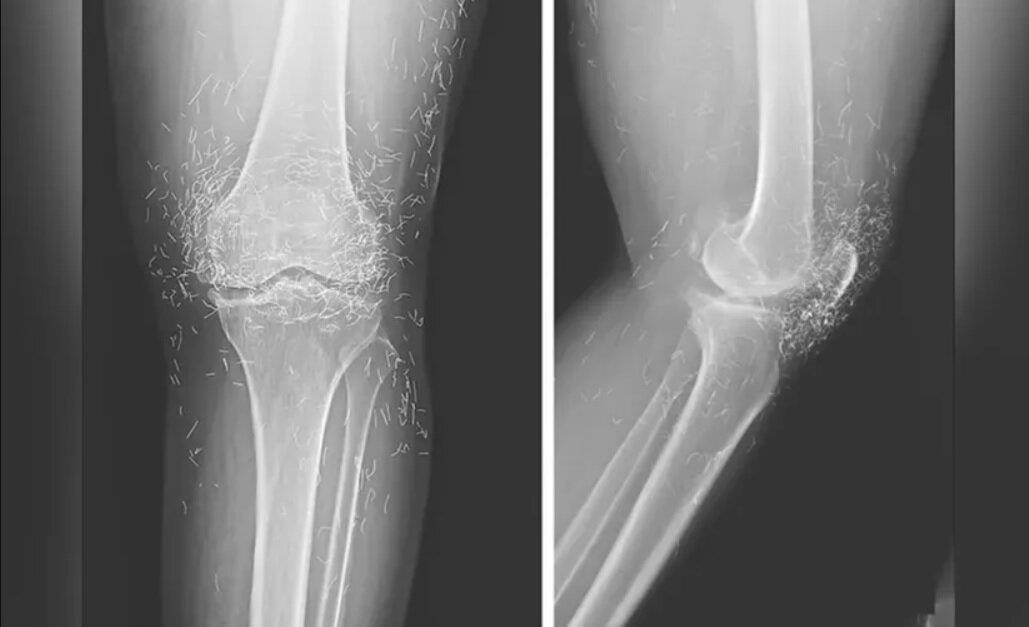

اما این روش هم نه‌تنها دردی از این زن دوا نکرد، بلکه زانودرد او را هم شدت بخشید. درنهایت او مجبور شد دوباره به بیمارستان مراجعه کند و پزشکان هنگام تصویربرداری از زانوها و دست‌های او متوجه صدها رشته‌ ریز و نازک از طلا در بافت‌های اطراف زانو و دست‌های این زن شدند.

طب سوزنی با رشته‌های طلا در برخی از کشورهای آسیایی، به‌ویژه میان سالمندان، رایج است اما پزشکان هشدار دادند این روش هیچ پشتوانه علمی ندارد و حتی ممکن است موجب عوارض خطرناکی چون ایجاد کیست، جابه‌جایی نخ‌ها در بدن، آسیب به بافت‌ها و حتی اشکال در انجام تصویربرداری MRI شود.